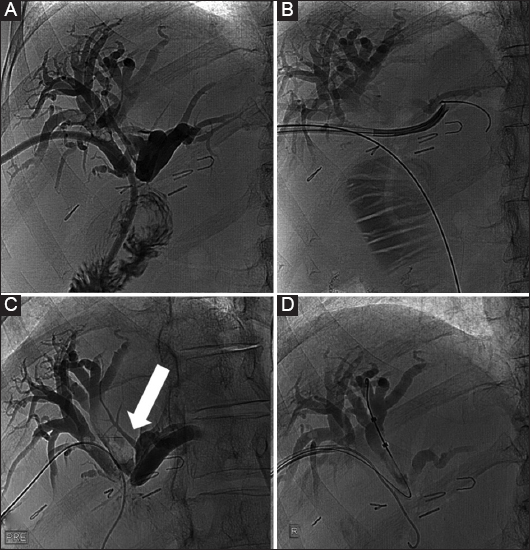

Figure 2 A 45-year-old female patient who developed benign biliary stenosis post laparoscopic cholecystectomy, with presence of stones. (A) Bilateral biliary drainage and dilation of the stenotic anastomosis with a high-pressure balloon (arrow). (B) Long-term drains with discoid end were left in situ for several months and the patient returned every 3 weeks for sequential dilation

Figure 3 A 48-year-old female patient with benign stenosis post biliodigestive anastomosis. (A) Initial drainage because of multiple small stones. (B) Cholangioscopic inspection to assess the presence of stones that were not visible in the cholangiogram. (C) Three months later, a new cholangiogram revealed the presence of a large stone (arrow). (D) The stone was retrieved with an extraction balloon. Presence of a “buddy-wire” to maintain access to the biliary tree